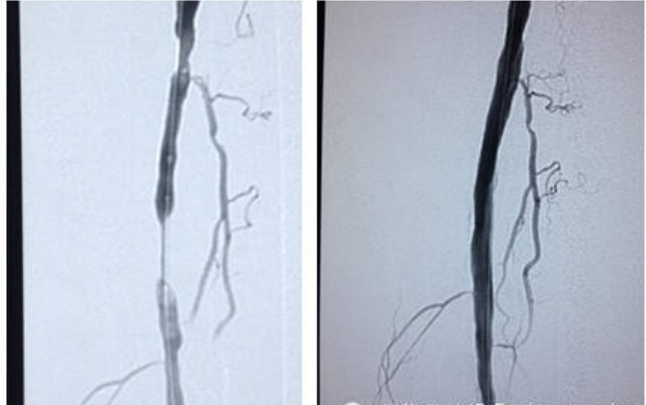

2014年12月20日,Reewarm®外周球囊扩张导管的首例临床病例植入在北京市中日友好医院顺利完成。

此次首例患者手术病灶长度非常长,应用 Reewarm 外周球囊扩张导管充分扩张,术后造影显示血管非常通畅,手术成功。

▲源自公司官网